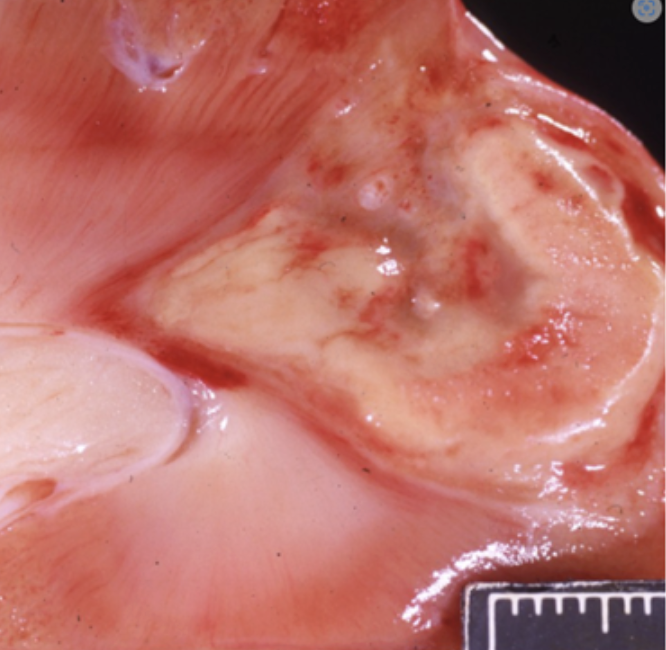

The smaller image on the left shows severe suppurative mastitis in a sheep. The image on the right shows a similar lesion which has healed. A. Describe and interpret the changes in the larger image on the right. (7 marks) B. Outline what occurred in the tissues as this lesion healed.

A. Affecting approximately 50% of the visible tissue, is a focally extensive, depression, in the centre of the mammary gland,(necrosis/tissue loss,1) which is filled with firm, white tissues (fibrosis, 1). B. Inflammation neutralises the insult --> M2 macrophage activated to stimulate healing and repair--> migration of fibroblasts and angiogenesis within wound bed, granulation tissue formation--> some glandular cell proliferation may occur but loss of supporting stroma means limited potential for regeneration (2) --> fibroblasts mature and synthesize collagen --> fibrosis --> myofibroblasts contract pulling wound edges together --> fibrosis remodels over time to add strength to the wound